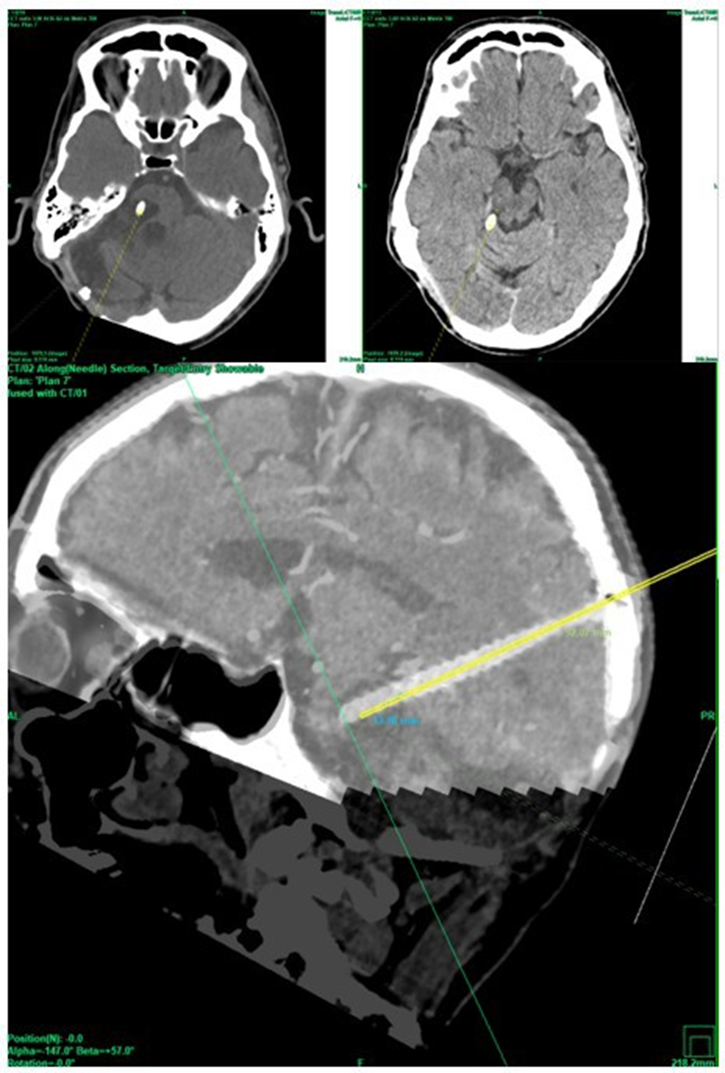

The patient was offered the alternative treatment of open fenestration and was informed that there was little to no experience regarding the outcome of this new procedure. Informed consent was obtained. On the day of the procedure, the patients received total intravenous anesthesia and a single shot of 1.5 g cefuroxime. The patient’s head was fixed in a aluminum ring (Precisis AG, Heidelberg, Germany) within a prone position. MR images with 2mm slices and a stereotactic CT were uploaded into the inomed iPS 6.0 software (inomed, Emmendingen, Germany). Several potential trajectories were evaluated to determine the safest surgical approach. A parietal transtentorial route was ultimately selected (Figure 4).

Figure 4 Stereotactic parietal transtentorial approach within the stereotactic CT scan (top) and within the MRI (bottom).